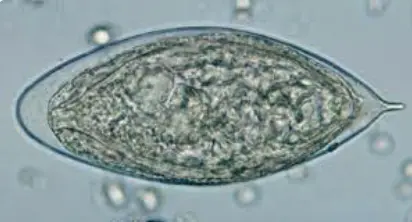

Giardia lamblia

schistosoma mansoni - terminal

schistosoma haematobium